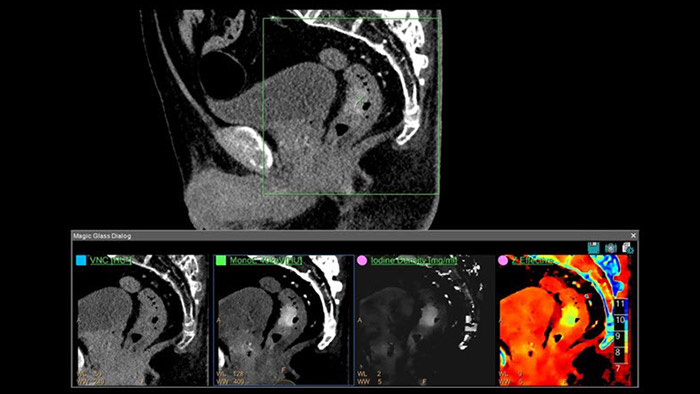

Les différentes cartographies spectrales les plus utilisées en routine

IQon Spectral CT est une nouvelle modalité scanner qui propose systématiquement plusieurs images conventionnelles et spectrales pour tout diagnostic. En routine, les cartes spectrales s’interprètent comme pour l’IRM par comparaison des différentes cartographies juxtaposées. Elles peuvent aussi être fusionnées les unes aux autres.

• Le mode mono énergie ou les cartes MonoE virtuelles (en unités Hounsfield) simulent un faisceau à RX monochromatique de 40 à 200 keV où l’utilisateur pourra faire varier l’énergie de 40 à 200 keV à l’aide d’un simple curseur sur l’image. La carte basse énergie de 40 KeV rehausse le contraste tissulaire ou iodé (l’atténuation maximale de l’iode est à 33 keV) et peut être utile dans le dépistage des lésions hyper vasculaires. Ce mode permet de diminuer les volumes de contraste injecté pour tout examen artériel, par exemple de 20 à 30cc pour une aorte abdominale standard ou un TAVI)*.

• La carte de densité d’Iode est une carte où le bruit a été soustrait, qui met en évidence le signal de l’iode uniquement. Elle est très souvent utilisée en comparaison de la Carte MonoE à 40 keV et permet de d’évaluer l’absorption du produit de contraste par les tissus avec la possibilité de mesurer des concentrations d’iode via un ROI.

• La Carte VNC ou « virtuel sans contraste » permet de diminuer la dose en supprimant la série sans injection. Les informations sans contraste sont extraites de la série injectée en supprimant la carte de l’iode.

• La carte d’imagerie paramétrique Z-Effectif reflète le numéro atomique moyen (de chaque pixel) et peut indiquer par exemple des zones graisseuses au sein des tissus.